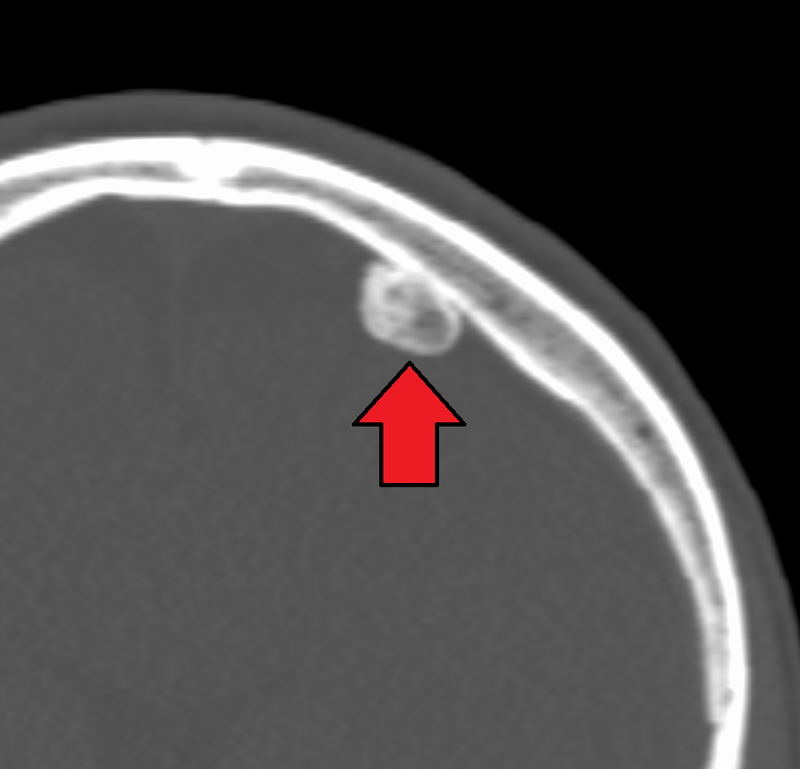

Osteoma most commonly arises on the surface of facial bones.

Osteomas are associated with Gardner syndrome.

Imaging of osteoid osteoma classically reveals a bony mass (< 2.0 cm) with a radiolucent core (osteoid).

The main differential to osteoid osteoma is an osteoblastoma.

Osteoblastomas are similar to osteoid osteomas, however osteoblastomas are larger bigger (> 2.0 cm), may develop in the vertebrae, and manifests as bone pain that is not relieved by aspirin.